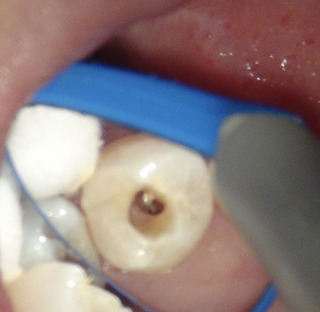

上から削っているところ なかなか根管口が見つからないので、レントゲンで位置を確認。

ガッタパーチャ(前医が入れた根の中に入っているお薬)が見えてきました。

GP(ガッタパーチャ)をほぼ外し、根管の中をケミカルで洗浄していきます。

やはりありました。もう一つの根管。

1根じゃなく2根管だったのね。

これで透過像の謎が解けました。

赤丸が2根管目。